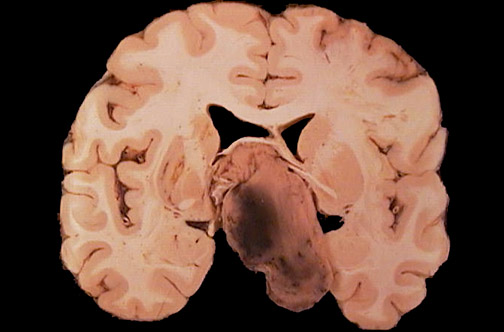

Image 6.4

This is a much more dramatic lesion seen at autopsy from a patient who was symptomatic.